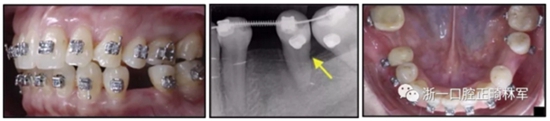

36歲;女性;尋求下頜左后方區(qū)域間隙管理的建議(圖1和圖2),通過治療獲得了良好的牙頜面效果(圖3和圖4)。她被診斷患有骨性I類和代償性牙性II類錯合畸形,并且上頜左側(cè)尖牙缺失(圖1和2)。大約七年前,由于不可修復(fù)的齲齒,拔除了下頜左側(cè)第一和第二磨牙(圖5)。37相鄰的第三磨牙向近中移動并傾斜入間隙,導致無牙頜間隙減小至約14 mm(圖2和圖5)。臨床和影像學評估顯示多發(fā)性齲損和在下頜右側(cè)567處有一不良的固定橋修復(fù)體(圖1和5)。此外,下頜左中切牙缺失,造成下頜中線向左側(cè)偏移約3 mm(圖1和圖2)?;颊咦栽V,她的右上第一前磨牙和左上尖牙在13歲時由其家庭牙醫(yī)拔除,因為它們被阻塞到頰側(cè)萌出(圖1)。上頜第二磨牙缺失(未知病因),并且相鄰的第三磨牙已經(jīng)轉(zhuǎn)移到第二磨牙間隙中。如補充材料所示,美國正畸學差異指數(shù)DI是28分。種植體部位(下頜左側(cè)和右側(cè)第一磨牙)由于復(fù)雜性得到額外4分(補充材料)。

圖1. 治療前面部和口內(nèi)照片

圖5. 治療前的側(cè)位片(上圖)和全景(下圖)的X光片